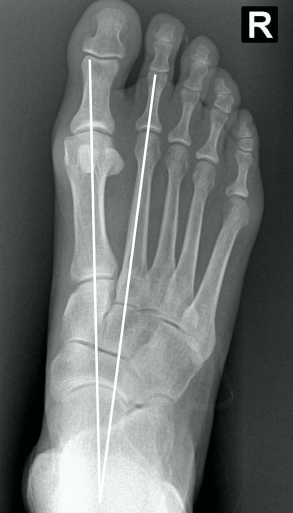

• Na avaliação radiográfica em AP com carga, quais os principais ângulos a serem traçados?

• Ângulo de valgismo do hálux (metatarsofalângico)

• Ângulo intermetatarsal

• Ângulo de valgismo interfalângico do hálux

• Ângulo articular metatarsal distal (AAMD)

• Na radiografia em AP com carga, como é traçado o ângulo intermetatarsal?

• Ângulo entre o eixo longo do 1° e do 2° raio

• Normal → até 9°

• Leve → 9° a 12°

• Moderado → 13° a 15°

• Grave → > 16°

• Na radiografia em AP com carga, como é traçado o ângulo de valgismo do hálux (metatarsofalângico)?

• Ângulo entre o eixo longo do 1° mtt e o eixo longo da falange proximal

• Normal → até 15°

• Leve → < 25°

• Moderado → 25° a 40°

• Grave → > 40°